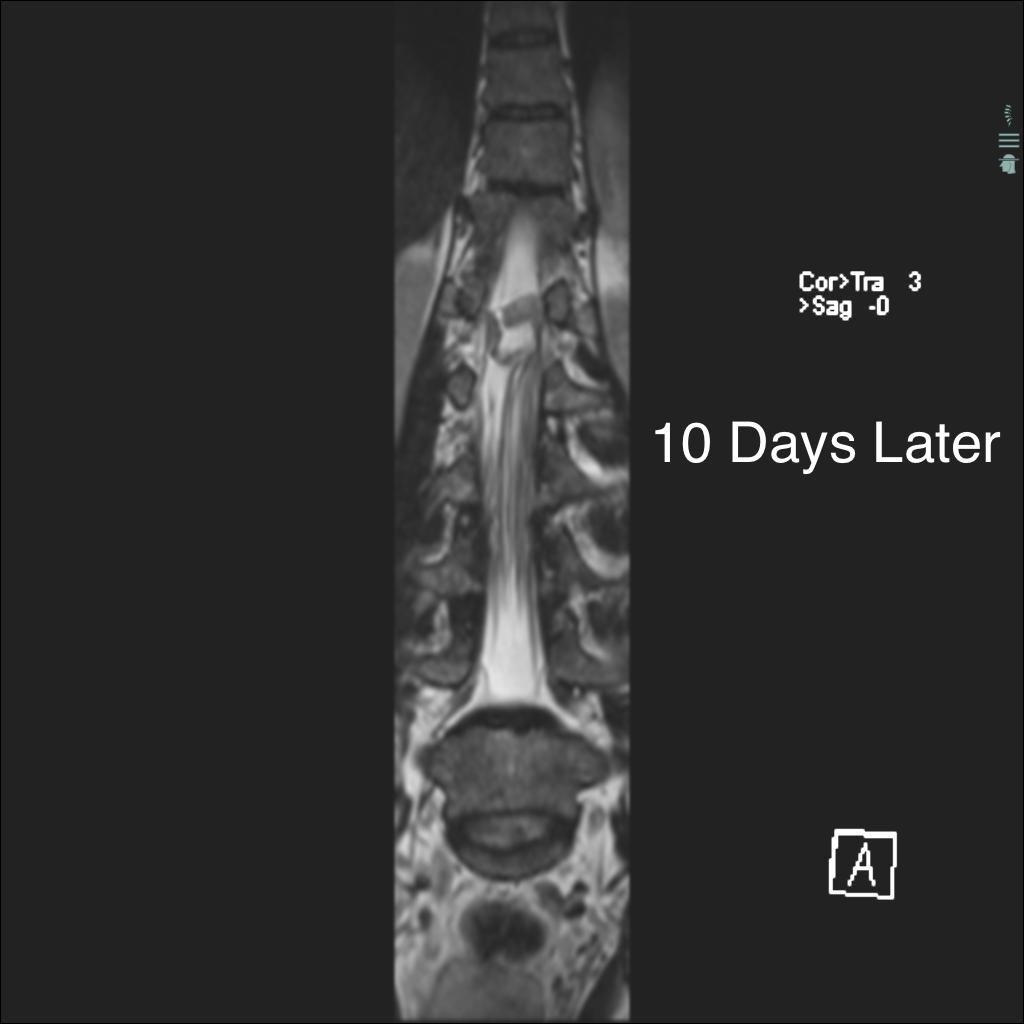

Case History: 40-year-old man with low back pain, right lower extremity paraesthesias, and incontinence. He presents 10 days later with worsening pain.

What is your diagnosis?